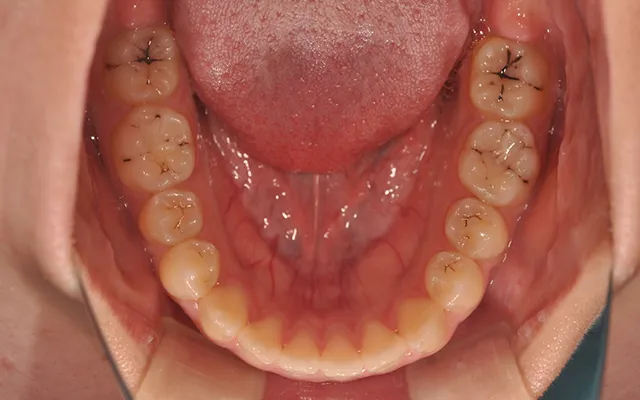

- BEFORE

-